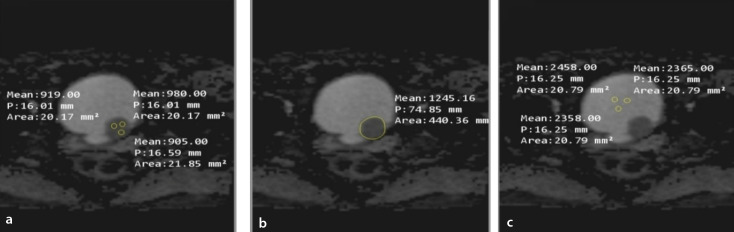

Methods: Patients with NMIBC, who were histopathologically confirmed between August 2020 and July 2023, were analyzed by 2 radiologists with different levels of experience. DCE semi-quantitative parameters such as wash-in rate (WiR), wash-out ratio (WoR), time to peak (TTP), and peak enhancement (PE) were calculated. ADC measurements were performed using the three-region-of-interest (ADCt) and whole volume (ADCw) methods; ADCt ratio (ADCtR) and ADCw ratio (ADCwR) were also calculated. Receiver operating characteristic curve analysis was performed to demonstrate the cut-off values of ADCt, ADCw, ADCtR, and ADCwR to differentiate low- and high-grade tumors. The intraclass correlation coefficient was used to evaluate inter-reader agreement.